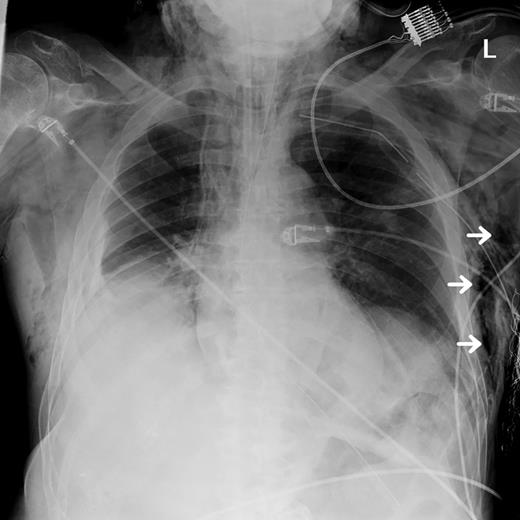

An 82-year-old male with past medical history of diabetes mellitus and alcohol abuse arrived by ambulance after being found unresponsive at the bottom of a flight of stairs with a scalp laceration. While en route to the hospital, two unsuccessful intubation attempts were made for a Glasgow coma scale (GCS) of 8. Upon arrival in the emergency department (ED), his GCS was determined to be 3 and was intubated with use of the Glidescope. Physical examination revealed decreased breath sounds on the left and crepitus over the left chest wall, suggestive of subcutaneous emphysema, and an immediate tube thoracostomy was performed prior to chest X-ray (CXR) to reduce the suspected pneumothorax. CXR post chest tube placement demonstrated large amounts of subcutaneous emphysema (Fig. 1 ), which was also visible on computed tomography (CT) scan along with evidence of pneumomediastinum and pneumoperitoneum (Fig. 2), with pneumoretroperitoneum and pneumoperitoneum present on abdominal CT scan (Fig. 3). As a result of the fall, he also sustained a fracture of the right frontal bone, fractures of the C2 and C3 vertebrae, and mild subarachnoid and subdural hemorrhage without shift. There were no intra-abdominal injuries found. He was admitted to the surgical intensive care unit (SICU) and maintained on mechanical ventilation, remaining hypotensive, hypothermic and mildly tachypneic, becoming increasingly unstable over the next 8 h. Due to the known pneumomediastinum, pneumoperitoneum and worsening instability, he was taken to the operating room for suspected viscus perforation and peritonitis. An exploratory laparotomy was performed, which revealed air within the lesser sac, but no evidence of bleeding or perforation. When closing the operative site, crepitus was also noted over the right chest wall, and a chest tube was placed into the right pleural space.

CXR performed after thoracostomy and chest tube placement displaying areas of subcutaneous emphysema (white arrows).